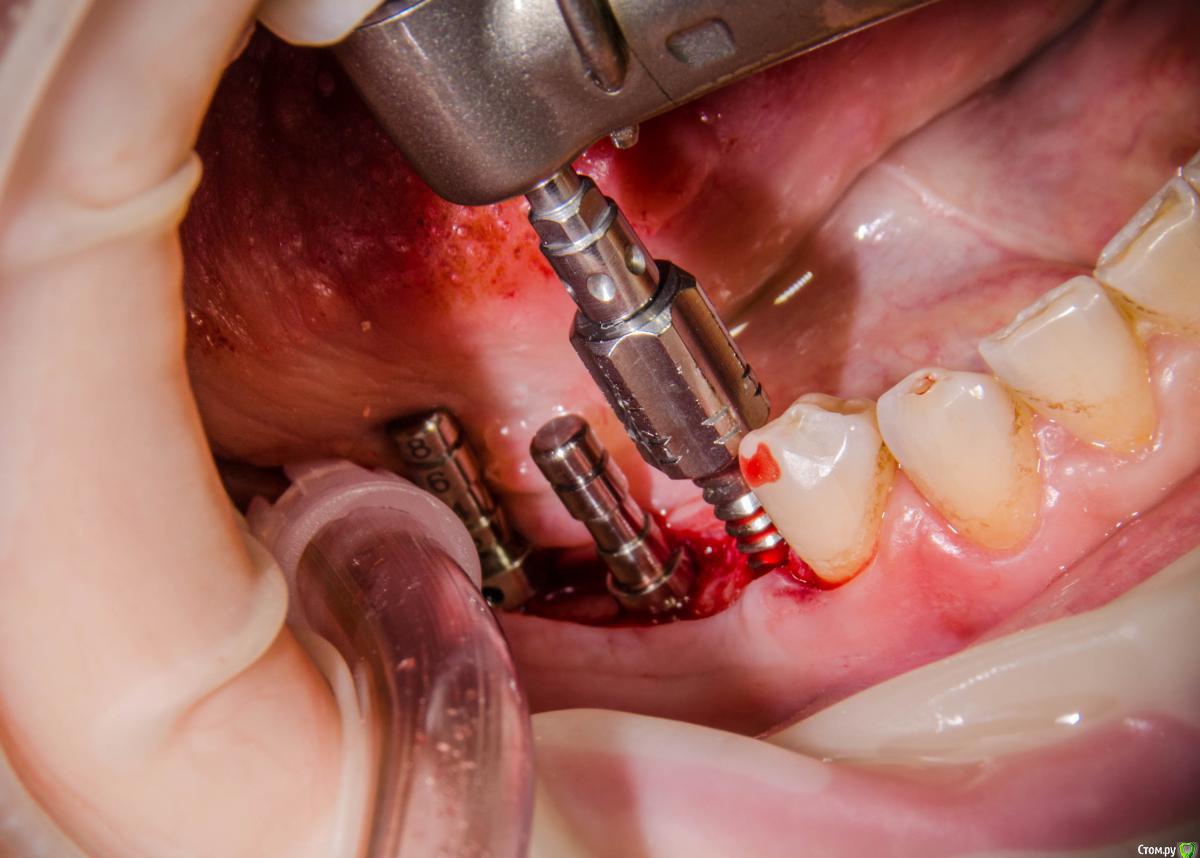

karasov Опубликовано 7 февраля, 2017 Поделиться Опубликовано 7 февраля, 2017 osstem esset kit? можно ли обойтись лишь одним диском из набора,а расширять самим имплантом по часовой - против часовой-по часовой....и тд? Ссылка на комментарий

kamranchick Опубликовано 7 февраля, 2017 Автор Поделиться Опубликовано 7 февраля, 2017 osstem esset kit? можно ли обойтись лишь одним диском из набора,а расширять самим имплантом по часовой - против часовой-по часовой....и тд?Нет, набор От Миса, пока вы вкручиваете-выкручиваете, пациент то языком дотронется имплантата то еще что то, лучше все подготовить и закрутиться и вы не сможете расширить имплантатом, он либо в ложе не войдет, ли торк будет сразу же очень высокий что в итоге сломает вестибулярку Ссылка на комментарий

kamranchick Опубликовано 8 февраля, 2017 Автор Поделиться Опубликовано 8 февраля, 2017 А что и какой размер ставили?Послабляющий распил не делали?я тут не делал распилы, тут нет расщепления3,5-8,5 Ссылка на комментарий